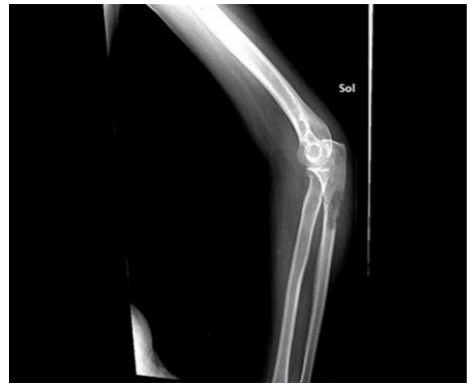

Before surgery: X-ray shows damage and risk of fracture in the proximal ulna.